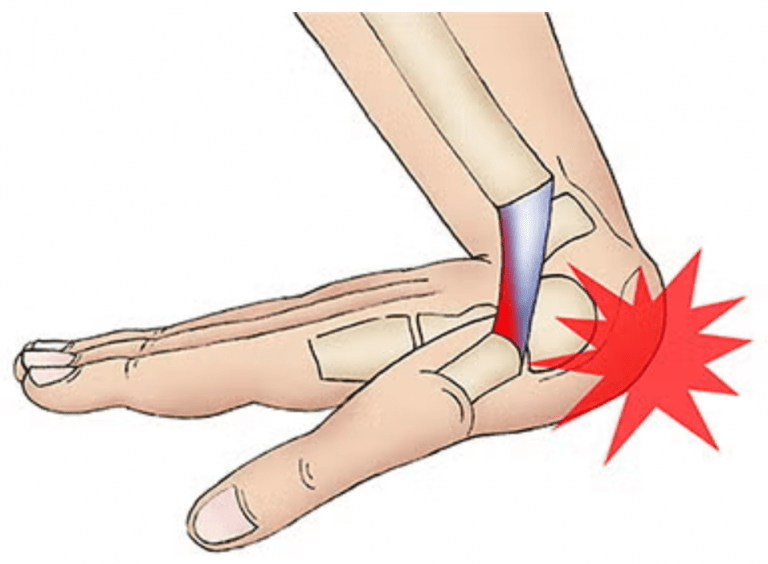

4. Esguinces de Muñeca

Un esguince de muñeca se produce cuando uno (o varios) ligamentos que dan estabilidad a las articulaciones de la muñeca, se estiran más allá de sus límites fisiológicos. Al producirse este movimiento, pueden producirse lesiones que van desde una distensión o una pequeño desgarro de los ligamentos, hasta una rotura parcial o total de los mismos. Es importante acudir al médico para recibir un diagnóstico diferencial y conocer el alcance de la lesión.

El mecanismo lesional más habitual en los esguinces de muñeca es la cuida sobre la palma de la mano